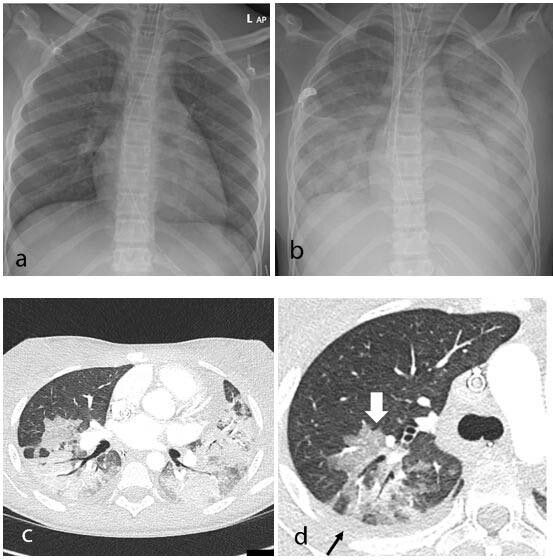

هذه الصورة توضح اثر الانتيرفيرون 👇🏼